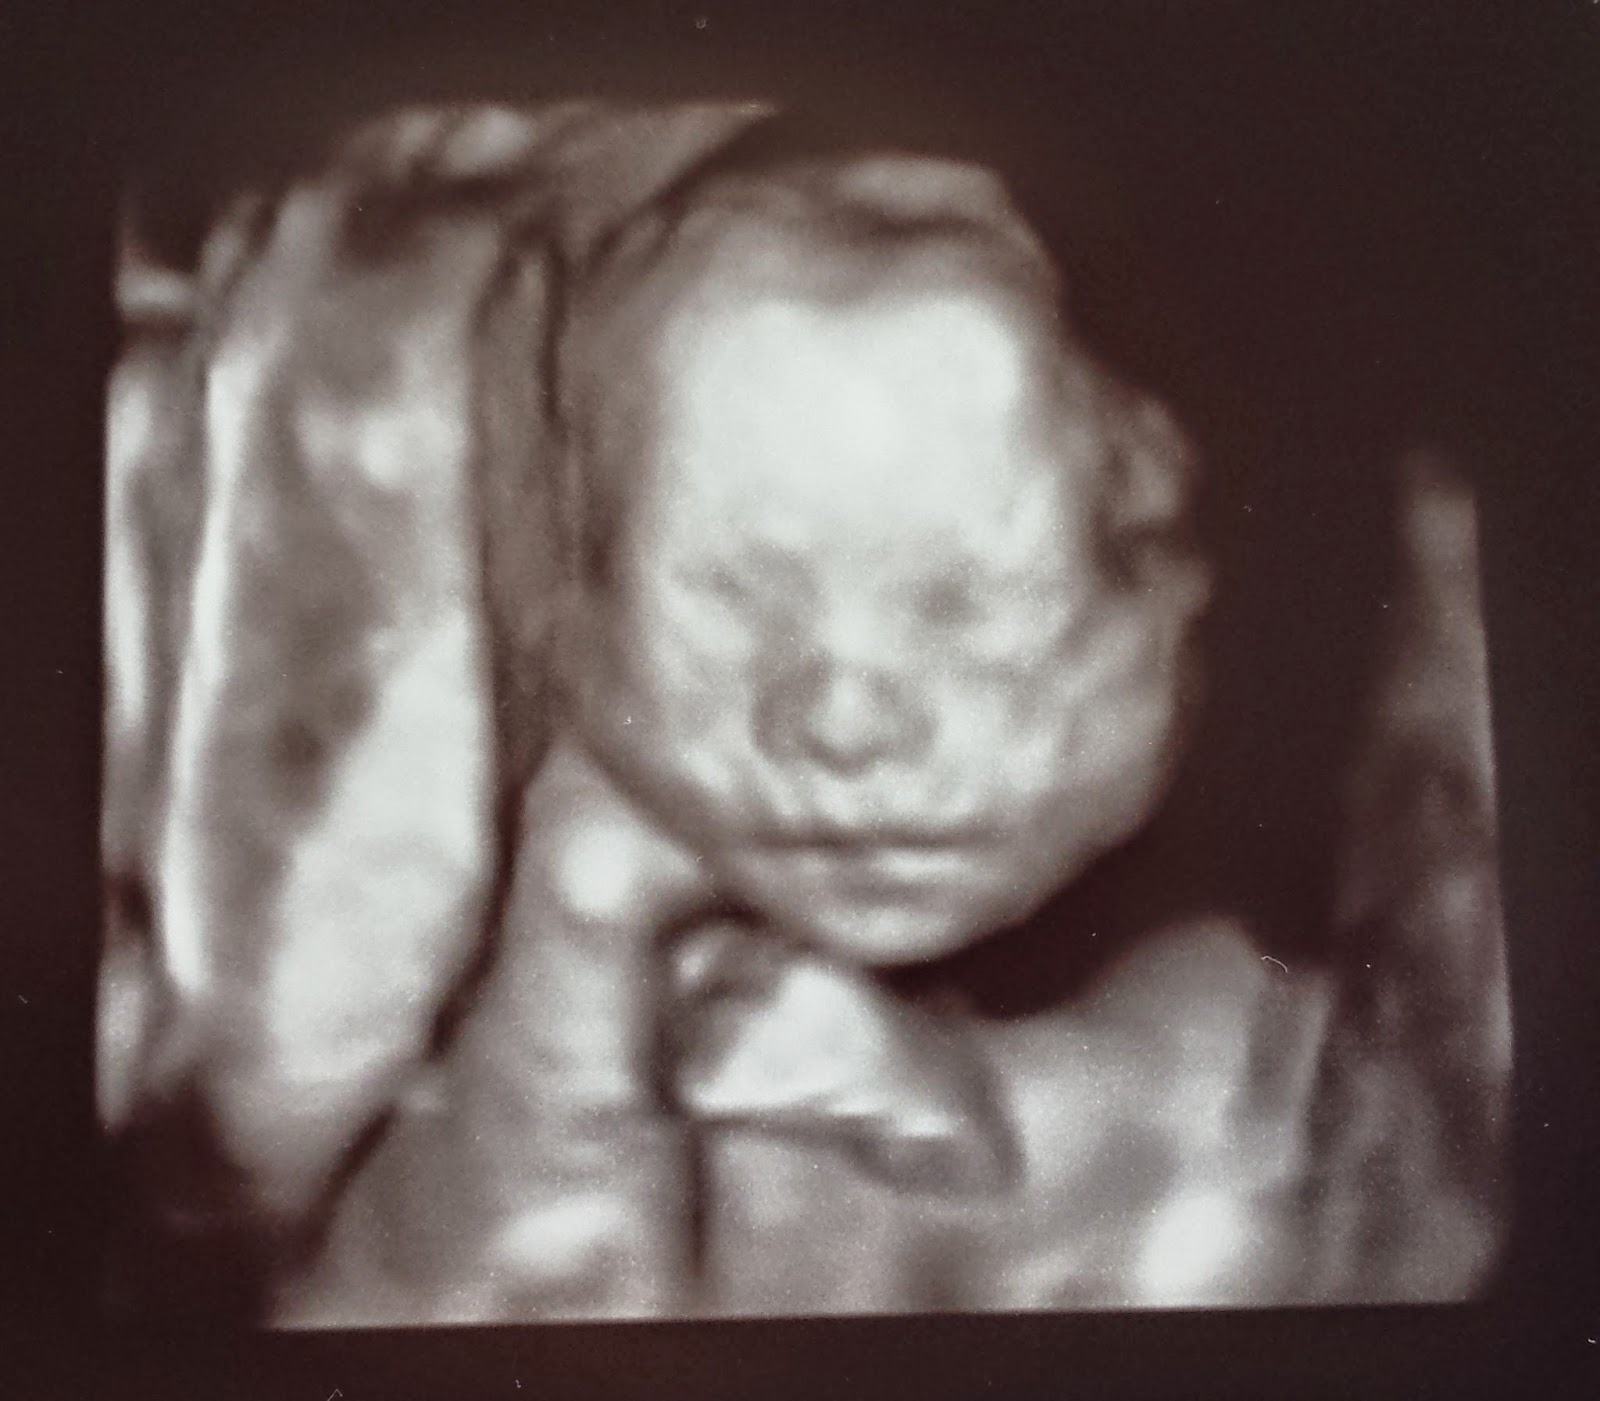

![]() |

| So shy. |